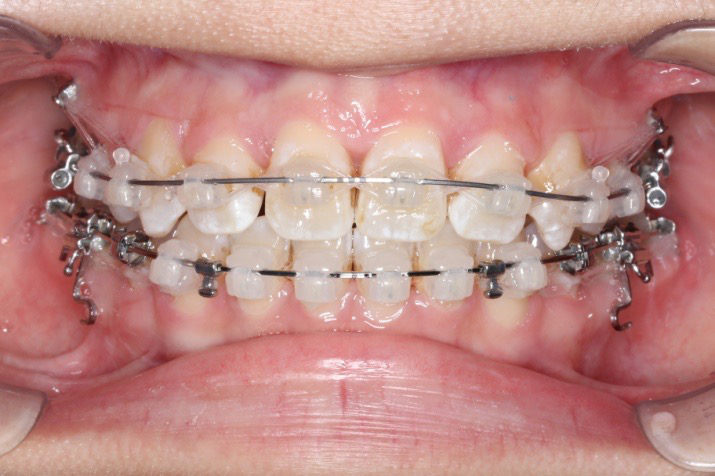

2018.04.20  间隙基本关闭,上颌重新整平,精调

2018.5.25  (19个月)拆TPA,16、26粘tube 上颌0.14*25cu-niti  下颌0.018*25niti2018.7.23  上颌 0.017*25TMA,下颌0.017*25ss43压低曲,双侧后牙垂直牵引

2018.09.29  15、43、16、17、11、21重粘,上0.016*25cu-niti 下0.018niti 上连扎

2018.11.14  术后侧面改善明显,露龈笑改善明显,笑弧笑线协调,颏部肌肉紧张度明显改善

2018.11.14  术后磨牙尖牙I类关系,中线齐,覆合,覆盖正常